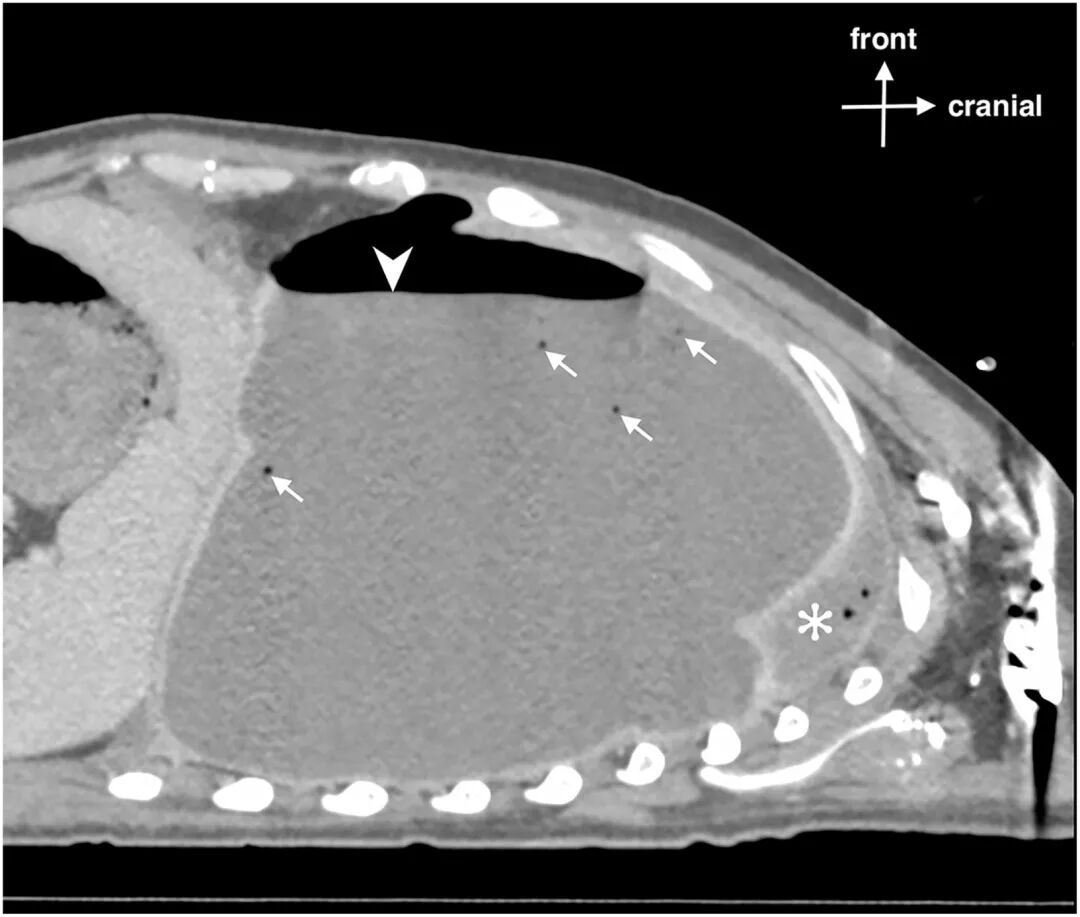

,可见浮游物,且肺滑动征消失。计算机断层扫描(CT)证实左侧广泛脓气胸

伴纵隔移位(图2)。

图2:胸部增强CT矢状位重建图像

图1超声显示气胸时平流层征(条形码征)。由于肺滑动征消失,M型超声图像全程表现为均匀的水平线(正常沙滩征模式消失)。胸膜线显示为清晰的高回声水平线。在B型图像右侧可见低回声胸腔积液(箭头)及游离气体(三角箭头),符合脓气胸表现。肺滑动征消失同时合并可见胸腔积液提示复杂胸膜病变。图2显示左侧大量胸腔积液,并可见气液平面(三角箭头),提示胸膜腔内存在游离气体。非重力依赖性游离气体(箭头)在积液最上方形成清晰、光滑的气液界面,符合液气胸(胸腔积液合并气体蓄积)表现。塌陷的左肺向上受压(星号)。上述表现符合脓气胸伴大量胸腔积液。